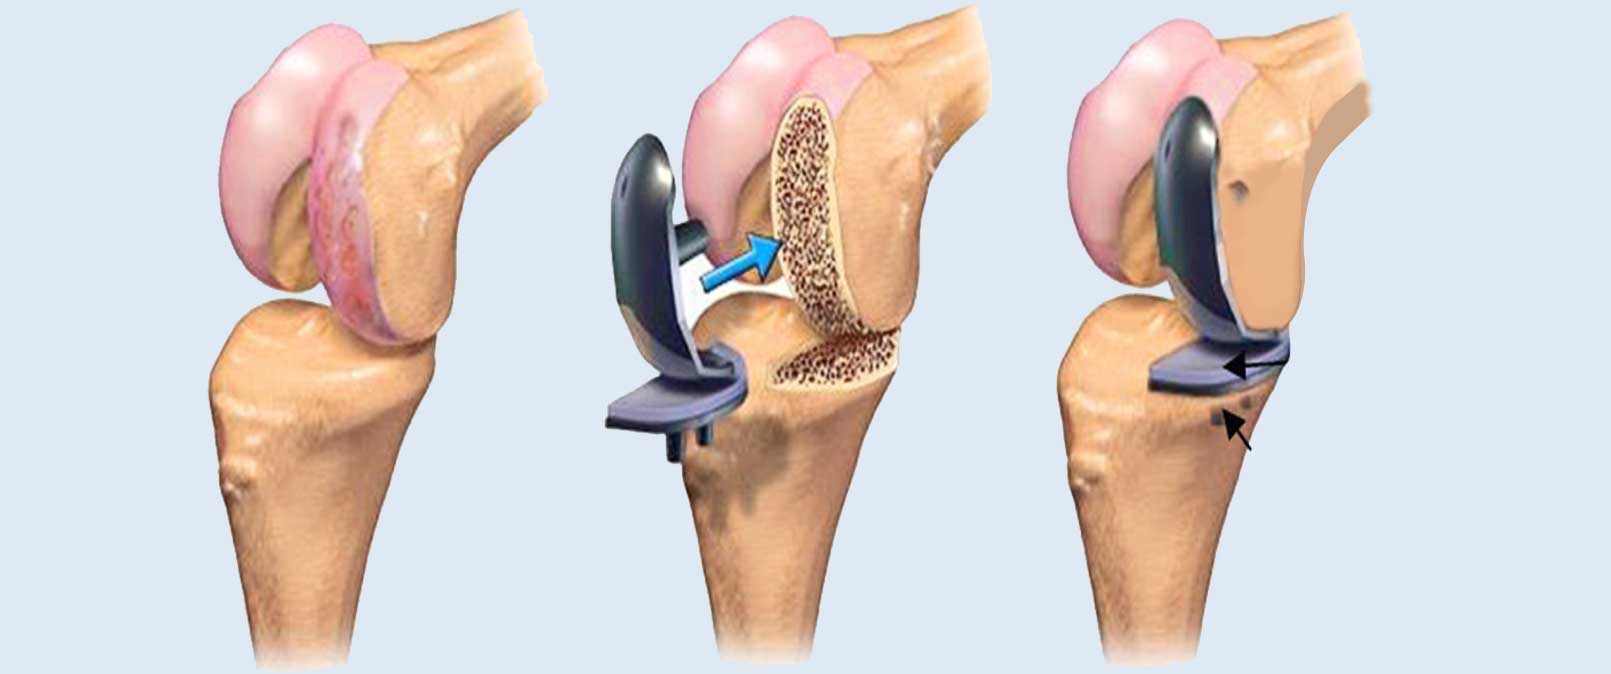

During a total joint replacement, the damaged bone and cartilage is resected and replaced by their equivalent prosthetic component.

Similarly, in knee replacement procedure the diseased bones are removed and replaced by their alternative prosthesis. The prosthesis placed mimics the shape and movement of a natural joint.